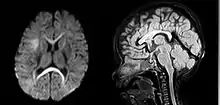

| An MRI of a patient with benign familial macrocephaly (male with head circumference > 60 cm) | |

Macrocephaly is a condition in which circumference of the human head is abnormally large.[1] It may be pathological or harmless, and can be a familial genetic characteristic. People diagnosed with macrocephaly will receive further medical tests to determine whether the syndrome is accompanied by particular disorders. Those with benign or familial macrocephaly are considered to have megalencephaly.

Benign or familial macrocephaly

Benign macrocephaly can occur without reason or be inherited by one or both parents (in which it is considered benign familial macrocephaly and is considered megalencephaly form of macrocephaly). Diagnoses for familial macrocephaly is determined by measuring the head circumference of both parents and comparing it to the child's. Benign and familial macrocephaly is not associated with neurological disorders.[2] While benign and familial macrocephaly does not result in neurological disorders, neurodevelopment will still be assessed.